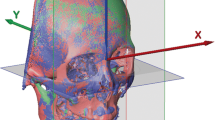

To compare the positional differences of the proximal ramus segment between T0 and T1, image registration and superimposition of the forehead and orbital areas (non-operated parts) were performed using the best-fit method (Figs 6–8). Accuracy of the registration was verified by checking the distance color map (Geomagic 3D software, 3D Systems, Rock Hill, SC, USA) and RMSD (3dMD Vultus software, 3dMD LLC, Atlanta, USA) between the T0 and T1 images, with green color (Fig. 7) and value ≤0.5 mm (Fig. 8) considered acceptable to ensure that the corresponding reference areas had maximum precision31,36. After the registration, the FHP and midsagittal plane (MSP, Table 5) were employed on the skull model for comparisons (Fig. 9). To measure the change in the proximal ramus segment before and after skeletofacial surgery, the same coordinate system was applied for both T0 and T1 mandible models. The PSP in the T0 image was created and transferred to the corresponding position in the T1 image. Thereafter, the two PSPs were used to measure the angular differences by using SimPlant O&O software (Figs 10–14). The PSP reference plane representing the proximal segment was examined for its postoperative rotation in pitch, roll and yaw directions (Table 5) in the right and left sides (n = 31) and overall proximal ramus segments (n = 62). Using ten randomly selected patients (20 mandible sides), the same examiner repeated all landmark localizations and measurements per axis (x, y, and z) in an interval of 2 weeks for error assessment.

T0 preoperative and T1 postoperative images of same clinical example as in Fig. 4. (Left) T0 and T1 images were superimposed on frontal and supraorbital bone. (Right) The color map indicated accurate registration of the two models on frontal and supraorbital bone showing the green color. The magnitude of the differences was greater in the lower facial parts, demonstrating the operative change.

Root-mean-square deviation (RMSD) was used to measure the accuracy of image superimposition, with value inferior to 0.5 mm considered acceptable. Same superimposed model as in Fig. 7.